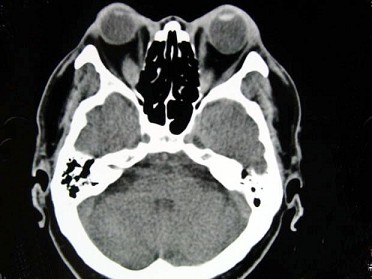

女,50岁,消瘦、多饮多食,脖子粗大,双侧眼球突出1年余,CT检查如图所示,应考虑为()

女,50岁,消瘦、多饮多食,脖子粗大,双侧眼球突出1年余,CT检查如图所示,应考虑为()<img border="0" style="width: 372px; h

[单选题]女,50岁,消瘦、多饮多食,脖子粗大,双侧眼球突出1年余,CT检查如图所示,应考虑为()A.眼型格氏病B.甲状腺眼病C.炎性假瘤D.横纹肌肉瘤E.眶部

女性50岁,消瘦、多饮多食,脖子粗大,双侧眼球突出,一年余,CT检查如图所示,应考虑为()<img border="0" style="width: 310px;

[单选题]女性50岁,消瘦、多饮多食,脖子粗大,双侧眼球突出,一年余,CT检查如图所示,应考虑为()A.眼型格氏病B.甲状腺眼病C.炎性假瘤D.横纹肌肉瘤E.眶

女性50岁,消瘦、多饮多食,脖子粗大,双侧眼球突出,一年余,CT检查如图所示,应考虑为()<img border="0" style="width: 198px;

[单选题]女性50岁,消瘦、多饮多食,脖子粗大,双侧眼球突出,一年余,CT检查如图所示,应考虑为()A.眼型格氏病B.甲状腺眼病C.炎性假瘤D.横纹肌肉瘤E.眶

女,50岁,消瘦、多饮多食,脖子粗大,双侧眼球突出1年余,CT检查如图所示,应考

[单选题]女,50岁,消瘦、多饮多食,脖子粗大,双侧眼球突出1年余,CT检查如图所示,应考虑为()A . 眼型格氏病B . 甲状腺眼病C . 炎性假瘤D . 横纹肌肉瘤E . 眶部结核

女性50岁,消瘦、多饮多食,脖子粗大,双侧眼球突出,一年余,CT检查如图所示,应

[单选题]女性50岁,消瘦、多饮多食,脖子粗大,双侧眼球突出,一年余,CT检查如图所示,应考虑为()A . 眼型格氏病B . 甲状腺眼病C . 炎性假瘤D . 横纹肌肉瘤E . 眶部结核